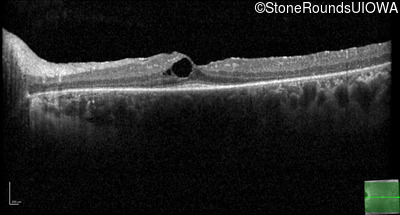

Optical Coherence Tomography - Right -

20/20 -1

Exemplar / OCT Stack